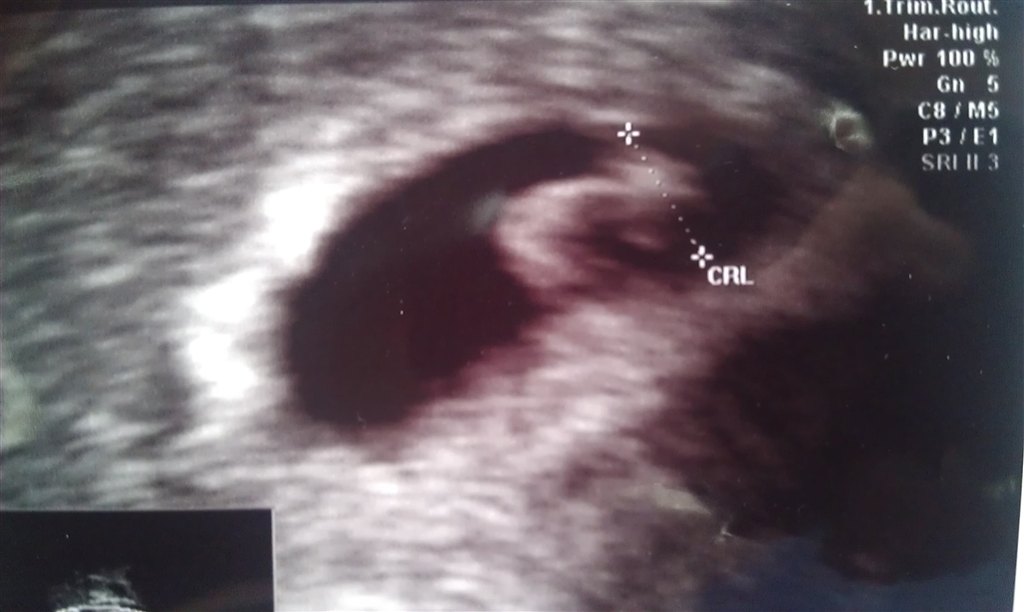

Se lige vores lille splint! er den ikke fin ?

vi er så lykkelige over familie forøgelsen.

Jeg var til tidlig scanning i dag for at fast slå termin,

og det belv den 4 maj

( nu håber vi bare at den bliver der  og har det godt )